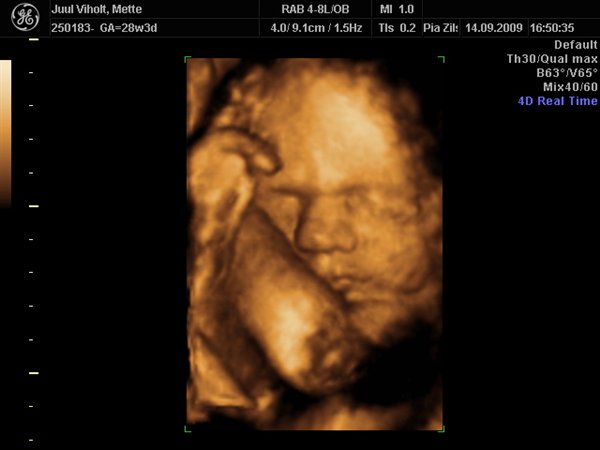

Hun ser dejlig ud, Tutski

Vi gav 1800 kr. for en scanningspakke med en kønsscanning i 17-18 uge og en 3D mellem uge 28-32.

Til 3D scanningen fik i 70 billeder printet OG på Cd, og hele scanningen med lyd på DVD.